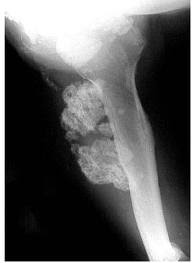

Bone And Soft Tissue Tumors Of Hip And Pelvis European Journal Of Radiology from els-jbs-prod-cdn.jbs.elsevierhealth.com One of the earliest signs of bone cancer is pain and swelling in the area where a tumour is located. Childhood osteosarcoma usually starts in areas where bone grows quickly such as the ends of long bones of the legs and arms. When these cancers in the bone are looked at under a microscope, they look like the tissue they came from. 375 236 просмотров 375 тыс. Bone cancer signs and symptoms. With osteosarcoma, cancerous cells produce bone, generally in the bones of the arm or leg. However, osteosarcoma can develop in any bone, including the bones of the pelvis (hips), shoulder, and jaw. Bowel preparation cleansing early warning signs of cancer signs that indicate that there may be a malignant growth in the body.

Osteosarcoma Physiopedia from www.physio-pedia.com When these cancers in the bone are looked at under a microscope, they look like the tissue they came from. Certain types emerge most often in the long bones of the arms and legs, while others occur most often in the pelvis, legs, ribs, and spine. However, the symptoms will start showing from an early age before a final diagnosis is made. Bone cancer occurring in the pelvis may cause lower back pain and sciatica. Bone cancer signs and symptoms. When to see your doctor about prostate cancer symptoms. How is bone cancer diagnosed? It can grow in any of the bones in the body.

Bone Tumor Types Symptoms Treatment Survival Period from www.epainassist.com The bones become fragile due to the formation of a malignant cancerous tumor with the bones or soft tissues near them. Bone pain can cause a dull or deep ache in a bone or bone region (e.g., back, pelvis, legs fractures: Although fever is rarely an early sign of bone cancer, it is a sign that the body is fighting an infection or illness. Pain is the most common sign of bone cancer, and may become more noticeable as the tumor grows. Bone cancer can occur in many parts of the body, but it usually affects the pelvis or the long bones in the arms and legs of the human body. Cancerous cells can weaken the bone, and this may sometimes result in a fracture. The most common signs of pelvic bone. The signs and symptoms of bone cancer in children vary from bone to bone.